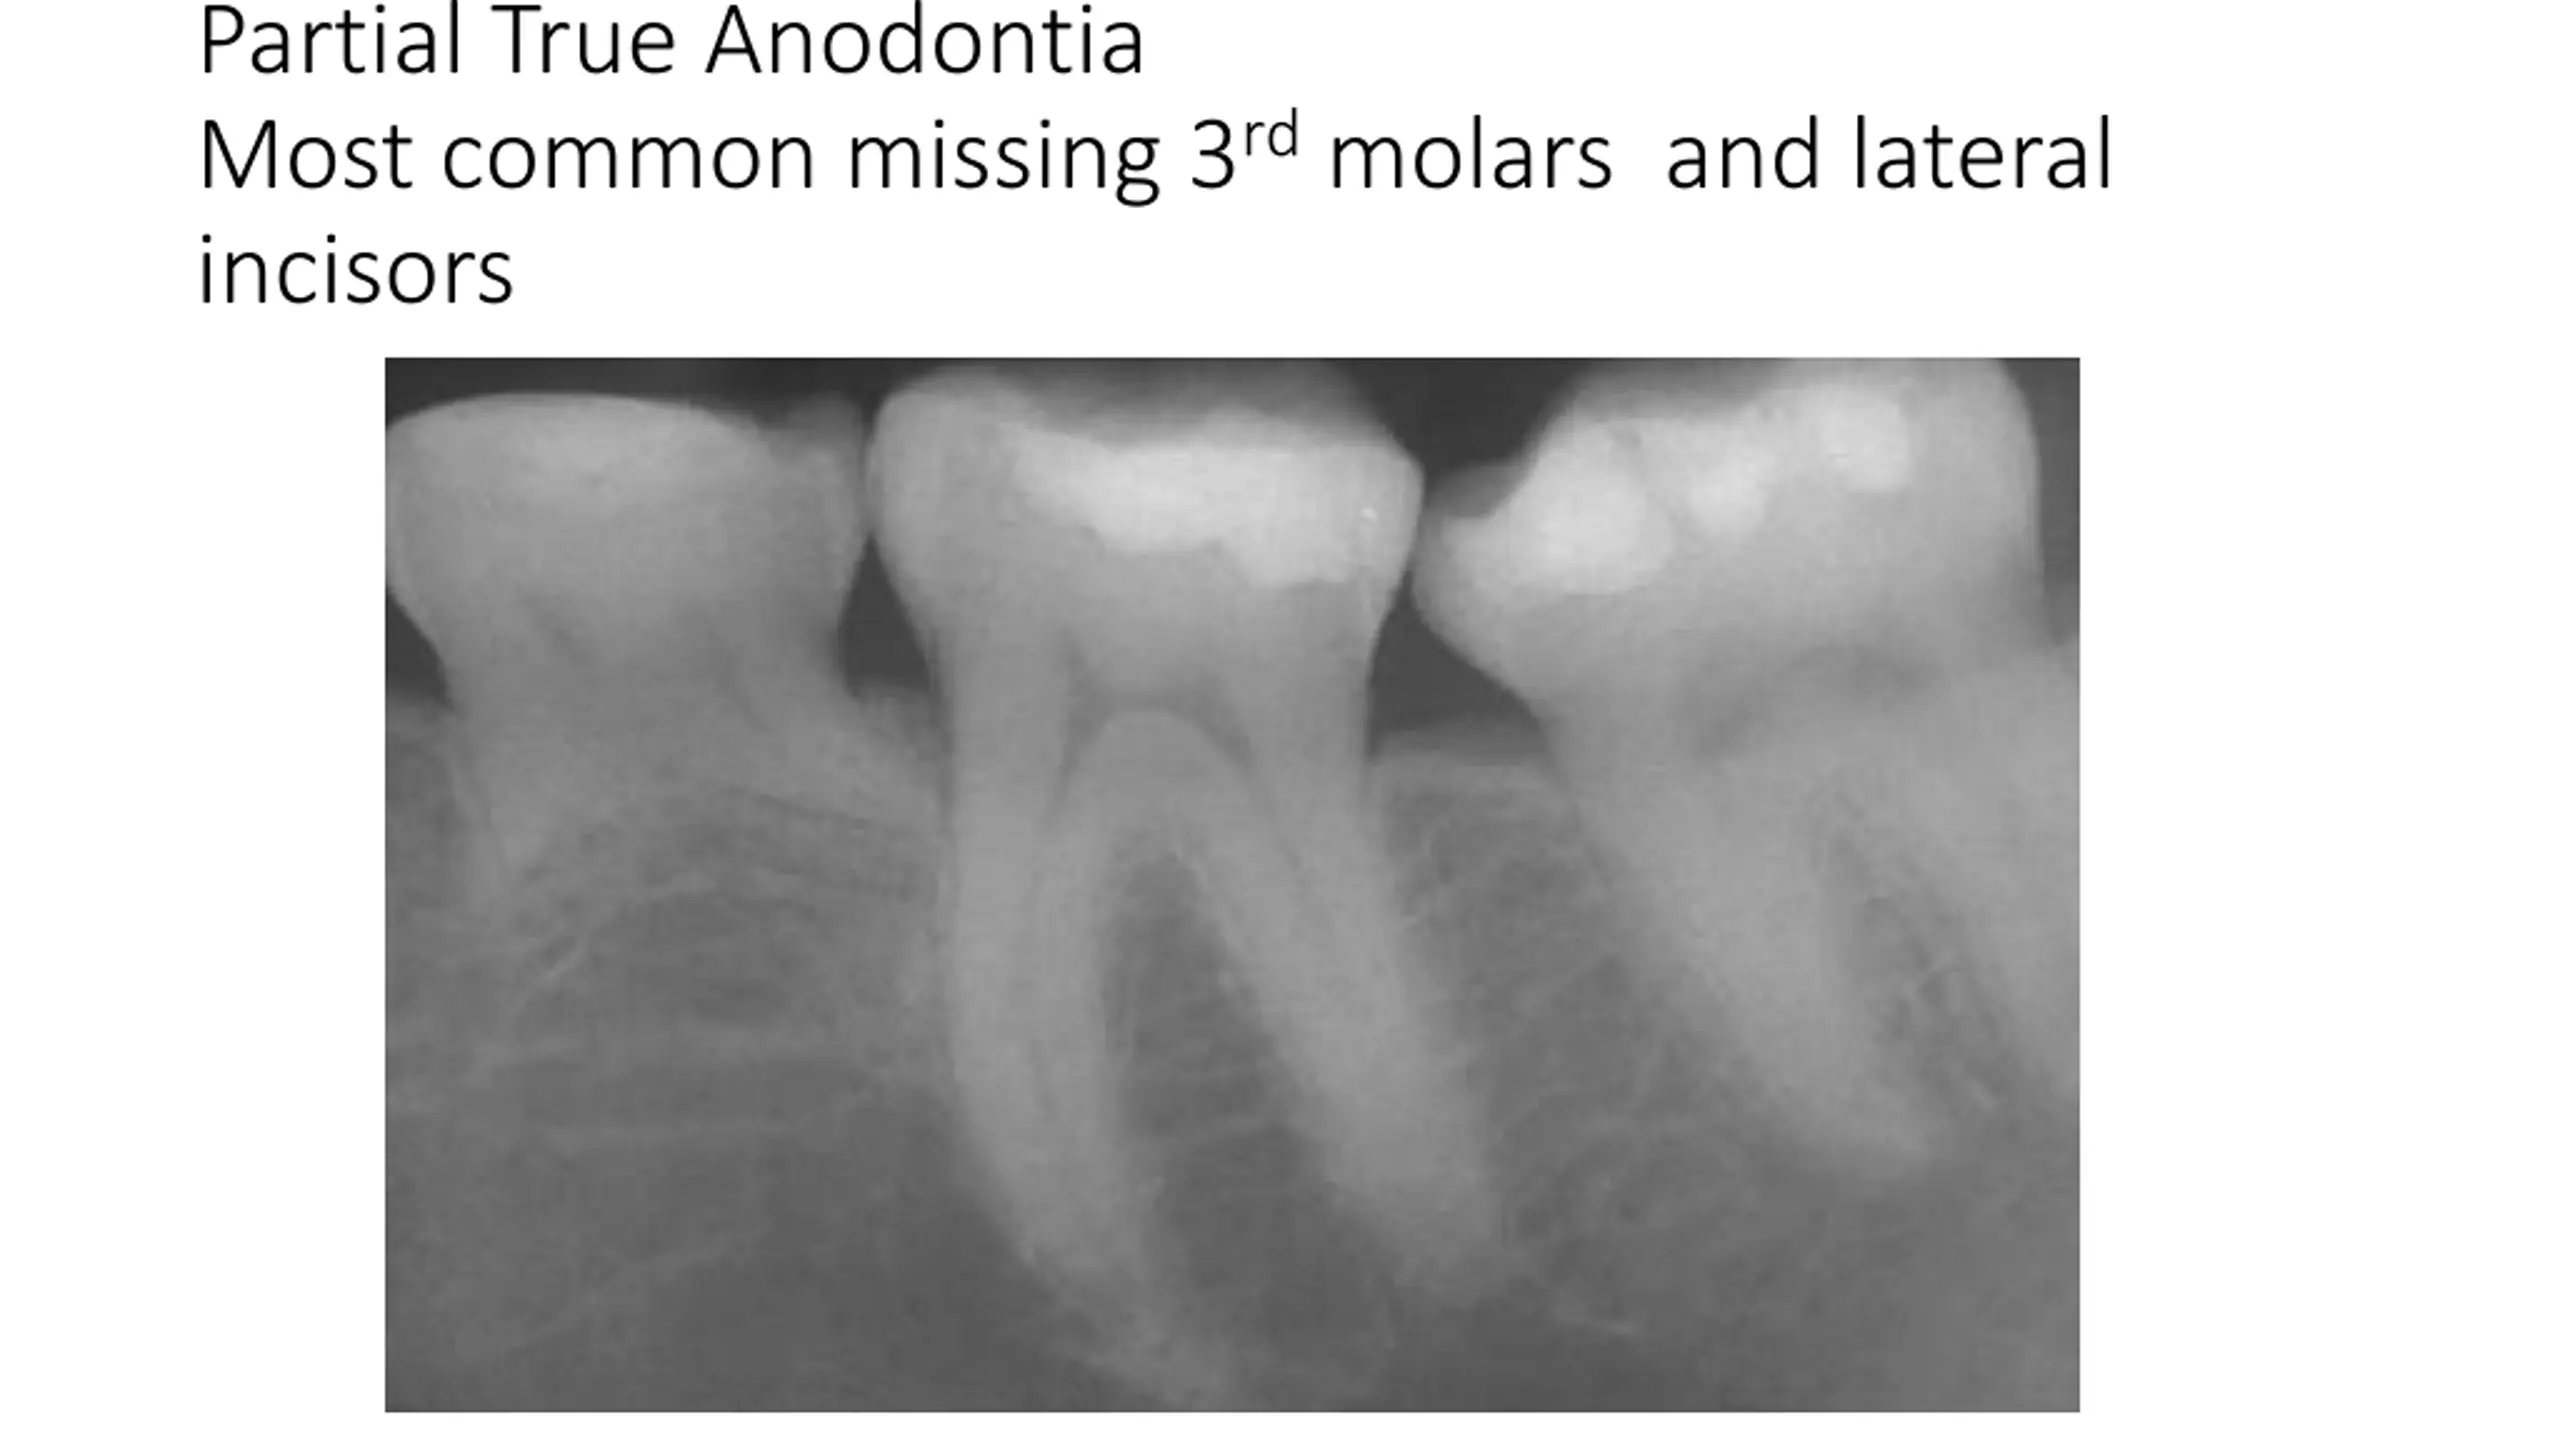

Partial True Anodontia Most common missing 3rdmolars and lateral incisors